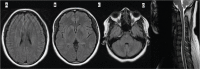

Stimulation of the immune response after vaccination can occasionally result in adverse effects, including demyelination of the central nervous system. The most common presentation of postvaccination demyelination is acute disseminated encephalomyelitis, but cases of optic neuritis, transverse myelitis, and multiple sclerosis relapses have been reported. More recently, an increasing number of postvaccination neuromyelitis optica spectrum disorder (NMOSD) cases have surfaced in the literature, especially in patients with aquaporin-4 antibodies. In this article, we report an unusual case of myelin oligodendrocyte glycoprotein antibody-related NMOSD after the receipt of multiple vaccines in a first-trimester pregnant woman from Africa. We review the reported cases of postvaccination demyelination in the past decade, with a focus on the relationship between NMOSD and vaccination in patients with aquaporin-4 or myelin oligodendrocyte glycoprotein antibodies. Finally, we discuss the clinical relevance of the present case and similar reported cases as it relates to patient care in the neuroimmunology clinic and identify potential areas for future research.